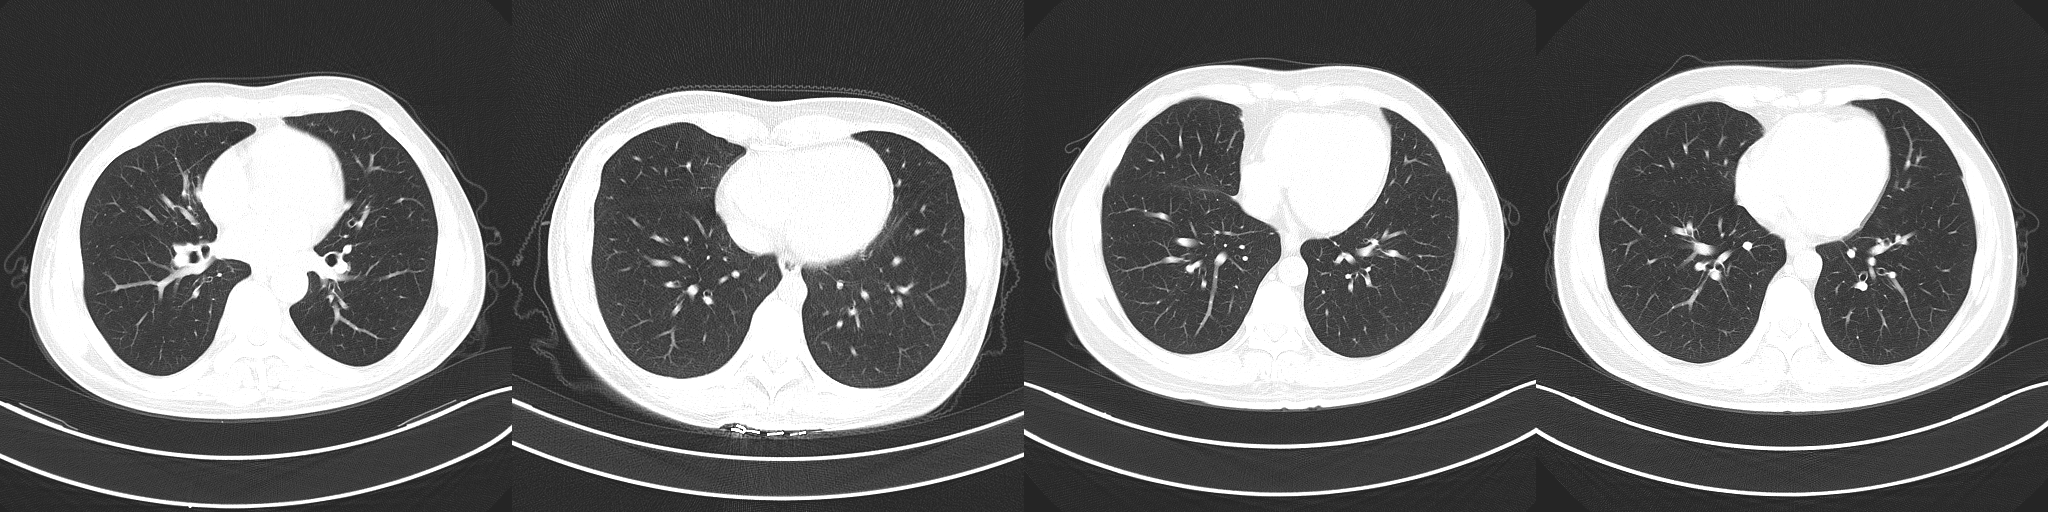

In early studies, it was found that certain abnormalities in chest CT images are indicative of COVID-19 infection, with ground-glass opacities, patchy shadows, crazy-paving pattern, and consolidation being some of the most commonly reported abnormalities, typically with bilateral involvement [11, 12, 13, 14, 5, 4, 6]. Moreover, some studies have found that abnormalities in a patient’s chest CT scan due to COVID-19 infection may be present despite a negative RT-PCR test [5, 4, 6]. However, as illustrated in Figure 1, these imaging abnormalities may not be specific to COVID-19 infection, and the visual differences between COVID-19-related abnormalities and other abnormalities can be quite subtle. As a result, the performance of radiologists in distinguishing COVID-19-related abnormalities from abnormalities of other etiology may vary considerably [15, 16]. For radiologists, visual analysis of CT scans is also a time-consuming manual task, particularly when patient volume is high or in large studies.

Figure 1: Example chest CT abnormalities in (a) a patient with COVID-19 pneumonia, and (b) a patient with non-COVID-19 pneumonia. It can be observed that visual difference in abnormalities between COVID-19 pneumonia and non-COVID-19 penumonia can be quite subtle.